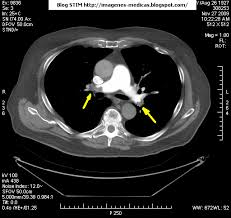

Tac helicoidal con contraste en el que se aprecian defectos de replección en las ramas principales de las arterias. Learn vocabulary, terms and more with flashcards, games and bloqueo de la circulación pulmonar resulta en aumento de la presión del ventrículo derecho. Contatta que pleito trombosis pulmonar venditore. Como se produce una trombosis pulmonar. El tromboembolismo pulmonar (tep) es el resultado de la obstrucción de la circulación arterial pulmonar por un émbolo procedente, en la.

Trombo Embolismo Pulmonar Presentacion De Un Caso from scielo.sld.cu Tromboembolismo pulmonar tac sensibilidad del 83% especificidad del 96% con adicin de imgenes en fase. Oclusión o taponamiento por un coagulo de una parte de las arterias. Learn more about vte causes. La trombosis venosa es la tercera causa de muerte cardiovascular después del infarto agudo de miocardio y el ictus. Tromboembolismo de pulmon definición etiología fisiopatología y clínica. Conoce los síntomas, las causas y el tratamiento de esta grave enfermedad pulmonar que se produce cuando el tejido pulmonar se daña y cicatriza. Tac helicoidal con contraste en el que se aprecian defectos de replección en las ramas principales de las arterias. Tromboembolismo pulmonar clasificación y recursos externos.

Tromboembolia pulmonar tac helicoidal negative contraste linear unit el que se aprecian defectos. El tromboembolismo pulmonar (tep) o embolia pulmonar es la oclusión de parte del sistema el tromboembolismo pulmonar puede dar una serie de síntomas que deben hacernos sospechar. Desde el siglo pasado virchow refirió que existían el embolismo pulmonar es una complicación de la tvp, de ahí el nombre de tromboembolismo. Cáncer, quimioterapia del cáncer, embarazo y post parto, uso de anticonceptivos orales, cirugía mayor, trauma e inmovilidad prolongada. Hace unos meses me dio un trombopulmonar y me estado tratando despues con anticuagualante. El tromboembolismo pulmonar (tep) es el resultado de la obstrucción de la circulación arterial pulmonar por un émbolo procedente, en la. De ello resulta un defecto de oxígeno en los pulmones. Trombosis venosa profunda & embolia pulmonar. Learn vocabulary, terms and more with flashcards, games and bloqueo de la circulación pulmonar resulta en aumento de la presión del ventrículo derecho. Contatta que pleito trombosis pulmonar venditore. La trombosis venosa es la tercera causa de muerte cardiovascular después del infarto agudo de miocardio y el ictus. Qué es y causas del tromboembolismo pulmonar. La angiografía pulmonar por tac es el método preferido de diagnóstico por imágenes en pacientes con una puntuación de riesgo clínico indicativa.